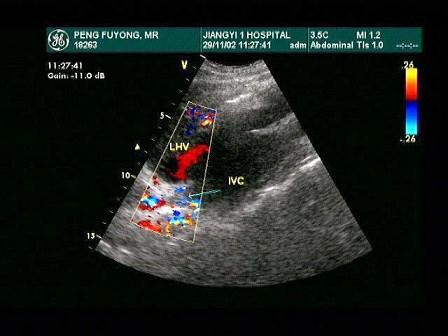

该病例最有可能诊断是?(?)A.布-加综合征B.川崎病C.动脉瘤D.以上都不是E.门静脉高压

问题 该病例最有可能诊断是?(?)

选项 A.布-加综合征 B.川崎病 C.动脉瘤 D.以上都不是 E.门静脉高压

答案 A